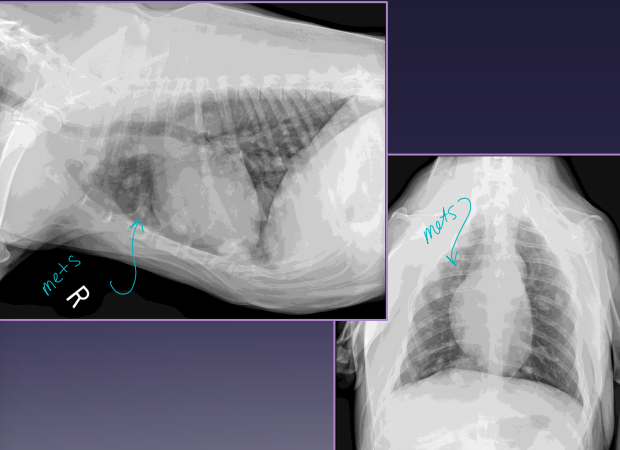

Splenic Neoplasia

Dt: Abd rads (mass effect, effusion, metastasis), US (mixed echotexture, cavitated lesions, enlarged spleen), biopsy

Xray chest for mets!